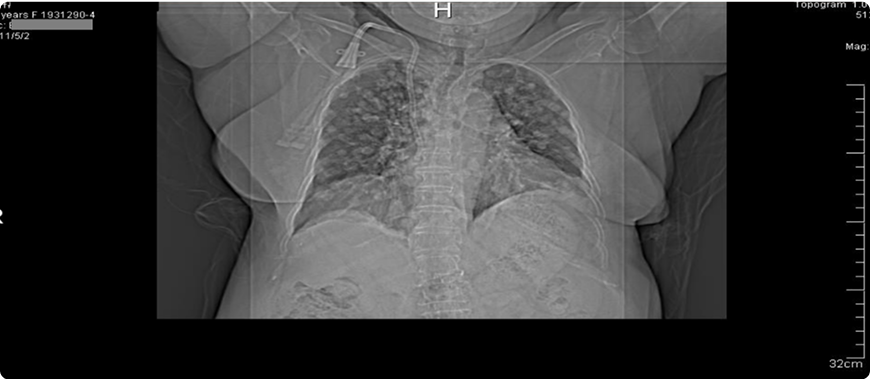

T様が2005年12月の定期健診で、腫瘍マーカーのCEAが異常な値を示し、その値は15ng/dl(標準値は5ng/dl)であった。更に検査を行ったところ、特に異常はなく、毎月定期健診をすることとなった。

半年後の定期健診(2006年6月)で腫瘍マーカーのCEAが断続的に上昇していたので、レントゲンを撮影した結果、肺癌と診断された。

肺癌と診断された後、2006年7月に緊急手術が行われ、胸を開いてみると、レントゲンで見つかった2センチメートルの2個の腫瘍のほかに、左肺葉と胸膜に転移が見つかり、なすすべがありませんでした。

そして、余命宣告を受けました。

その後T様は一年半、分子標的治療等を受け、癌をコントロールしていました。しかし、腫瘍マーカーのCEAの動きは激しく、癌の安定化には至りませんでした。そこで2008年にT様の友人である医師の紹介でアントロキノノール含有エキスの摂取を始めました。

T様はアントロキノノール含有エキスを服用し続け、毎月定期健診をしていたところ、病状は改善されていきました。そして一年後の2009年7月24日の各種検査でがん細胞は検出されなくなり、他の検査の数値も安定していました。